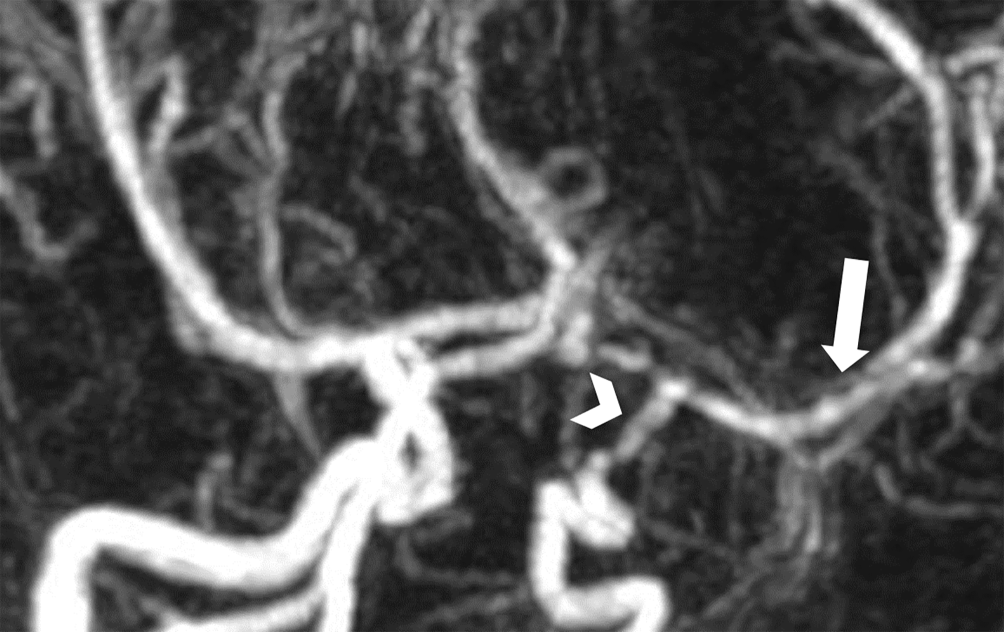

In der durchgeführten kranialen MRT (cMRT) zeigt sich eine nichtdemarkierte Diffusionsstörung im Mediastromgebiet links, genauer im Bereich der Basalganglien links mit Beteiligung der Inselrinde, ohne Nachweis eines Gefäßverschlusses oder -dissektion (Abb. 1 und 2).

Abb. 2

Kontrastmittelunterstützte MR-Angiographie offenbart Wandunregelmäßigkeiten und Stenose der distalen ACI. (Pfeilspitze) und des M1-Segments der ACM der linken Seite im Verlauf

Es wird die Diagnose eines kindlichen Schlaganfalls gestellt; weitere Differentialdiagnosen sind in Tab. 1 angeführt. Eine in der cMRT gezeigte Diffusionsrestriktion im Mediaversorgungsgebiet links erhärtet die Diagnose. Es wird im intensivmedizinischen Setting eine systemische Lysetherapie mit Alteplase (Actilyse®) in der Dosierung 0,9 mg/kg innerhalb eines Zeitfensters von 02:55 h nach Symptombeginn durchgeführt. In stabilem Allgemeinzustand kann der Patient in weiterer Folge am vierten Tag mit schlaffer Hemiparese und zentraler Fazialisparese rechts unter laufender kontinuierlicher Heparintherapie in der Dosierung 15 IE/kg/h mit einer Ziel-PTT im Normbereich zur Vorbeugung eines Rebound-Phänomens nach erfolgter Lysetherapie auf die Normalstation verlegt werden. Die cMRT am 7. Tag nach Symptombeginn mit Gefäßdarstellung zeigt Kaliberirregularitäten teilweise mit Stenosierungen im Bereich der distalen Arteria carotis interna, im A1-Segment der A. cerebri anterior sowie im M1-Segment der A. cerebri media links. Die rechts- und einseitige klinische Präsentation des Schlaganfalls, die fehlenden Entzündungszeichen, ein erhöhtes von-Willebrand-Antigen als Zeichen der Endothelaktivierung, die unilaterale Gefäßmanifestation sowie die Morphologie der Bildgebung sind somit passend zum Bild einer primären ZNS-Vaskulitis des Kindesalters („childhood primary angiitis of the central nervous system“, cPACNS). Es liegt der Subtyp einer idiopathischen Angiographie-positiven nichtprogredienten Großgefäßvaskulitis vor [24]. Therapeutisch erhält der Patient in weiterer Folge eine Methylprednisolon-Stoßtherapie in der Dosierung 20 mg/kg/Tag für 3 Tage mit anschließender oraler Therapie mit Prednisolon in der Dosierung 2 mg/kg/Tag, welche über 10 Wochen ausgeschlichen wird. Zudem werden eine Thrombozytenaggregationshemmung mit Acetylsalicylsäure 200 mg für 2 Jahre sowie eine Antikoagulation mit Enoxaparin 20 mg für 3 Monate veranlasst [5, 6]. Der Patient kann zur weiterführenden Rehabilitation an ein pädiatrisches Reha-Zentrum verlegt werden.